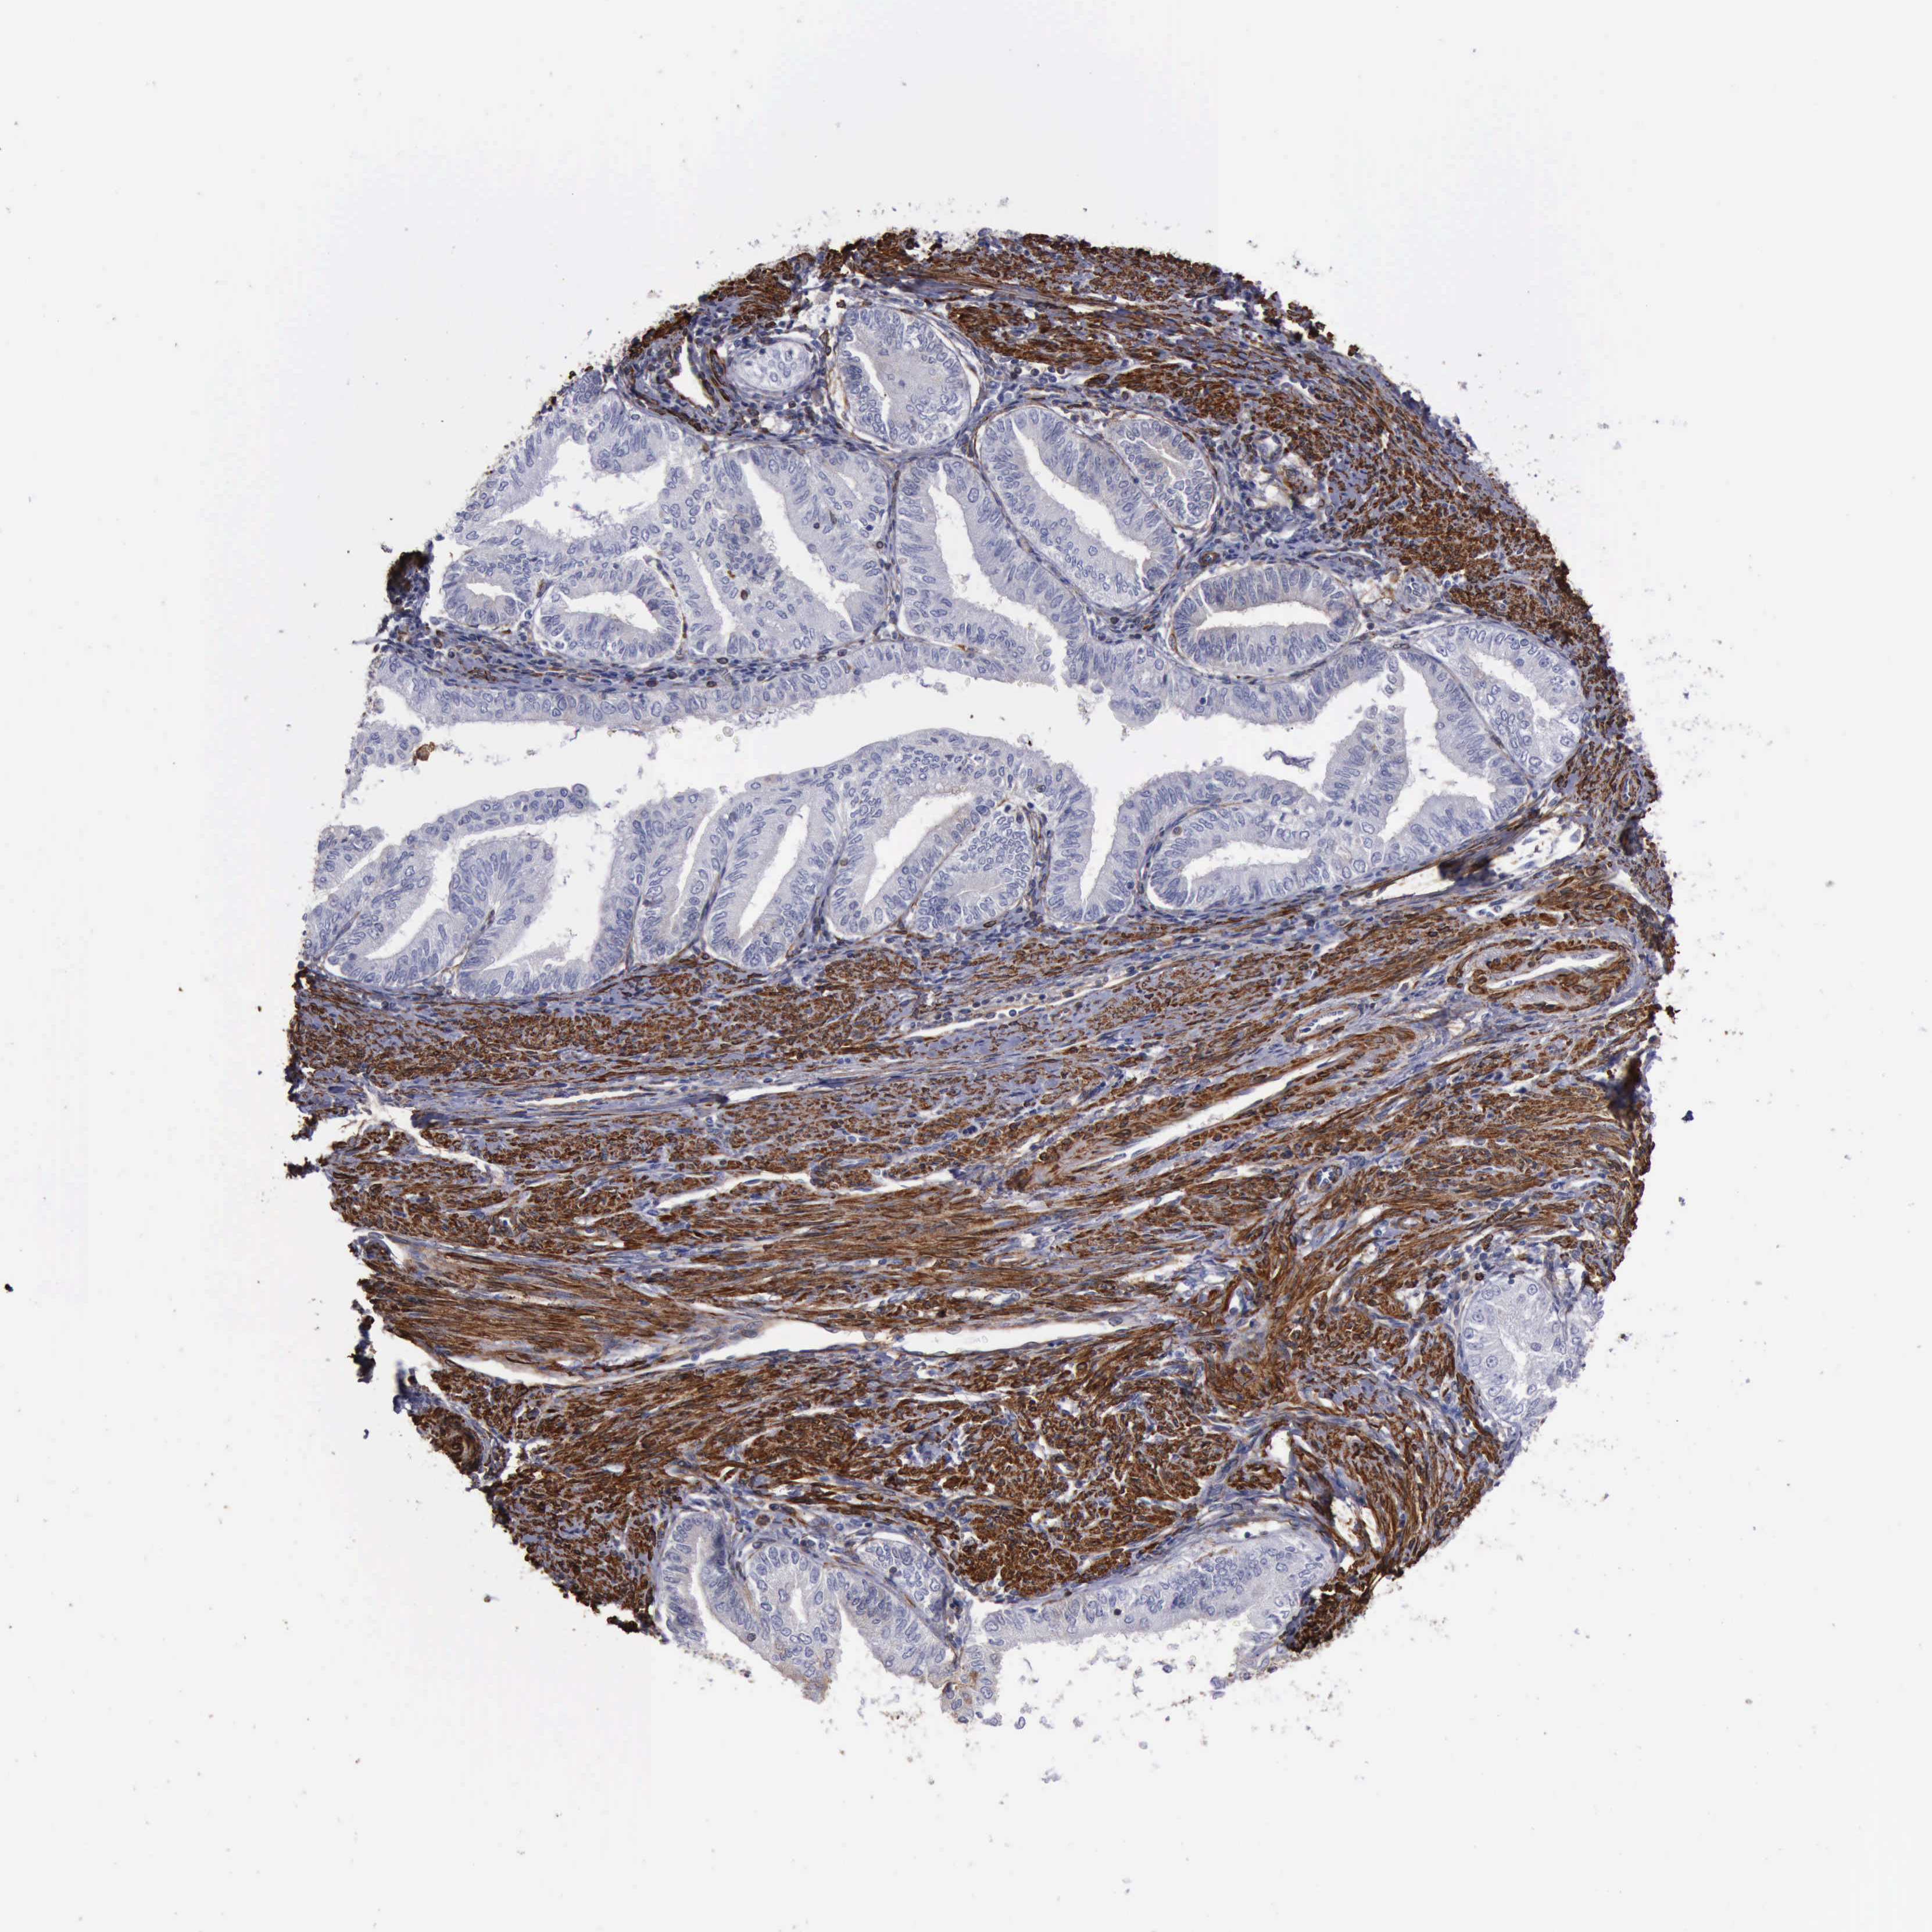

ENDOMETRIAL CANCER - Protein expressioni

A mouse-over function shows sample information and annotation data. Click on an image to view it in a full screen mode. Samples can be filtered based on level of antibody staining by selecting one or several of the following categories: high, medium, low and not detected. The assay and annotation is described here.

Note that samples used for immunohistochemistry by the Human Protein Atlas do not correspond to samples in the TCGA dataset.

Antibody stainingi

Antibody staining in the annotated cell types in the current human tissue is reported as not detected, low, medium, or high, based on conventional immunohistochemistry profiling in selected tissues. This score is based on the combination of the staining intensity and fraction of stained cells.

Each image is clickable and will lead to virtual microscopy that enables deeper exploration of all samples and also displays staining intensity scores, fraction scores and subcellular localization as well as patient and tissue information for each sample.

Antibody HPA001115

Antibody HPA002925

Antibody CAB000356

Staining

High

Medium

Low

Not detected

Intensity

Strong

Moderate

Weak

Negative

Quantity

>75%

75%-25%

<25%

None

Location

Nuclear

Cytoplasmic/membranous

Cytoplasmic/membranous,nuclear